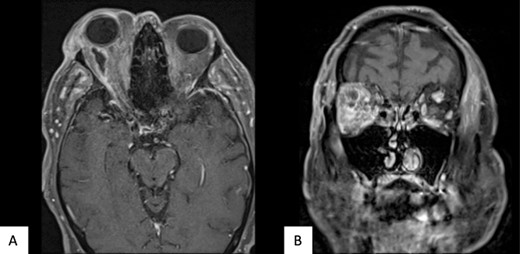

The patient underwent transconjunctival peritomy and drainage of the inferomedial abscess. However, vision regressed from hand movements to no light perception 5 days following initial drainage. Re-imaging of the orbit revealed a new retroorbital abscess accumulation superior-temporally (Fig. 4) that was also then drained. Both collections contained frank pus, and cultures also grew methicillin sensitive S. aureus, requiring a prolonged course of intravenous flucloxacillin and oral steroids. Subsequent MRI showed right lateral retroorbital abscess regression and less prominent retroorbital phlegmonous changes (Fig. 5). However, vision did not return to the patient’s eye.

Axial (A) and coronal (B) MRI T1 FS post contrast imaging demonstrating new, right sided posterosuperior, peripherally enhancing collection post drainage of previous collection.